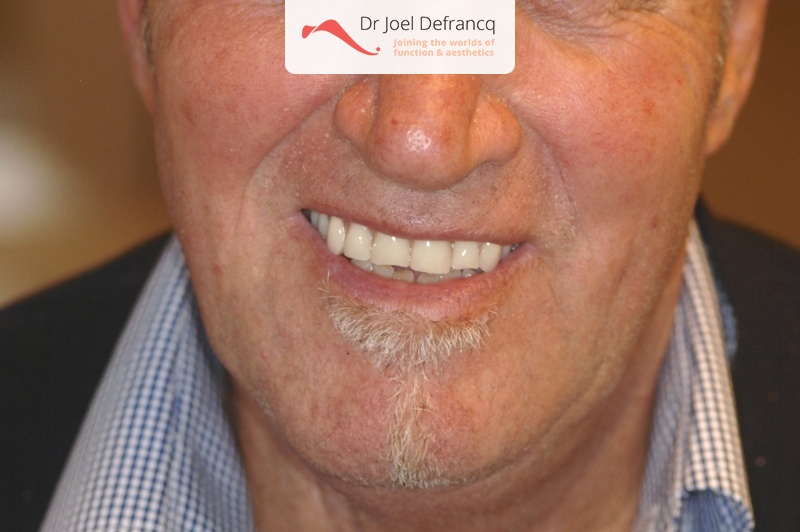

Maurice

Diagnose van het gezicht

Behandeling tandheelkundige implantaten